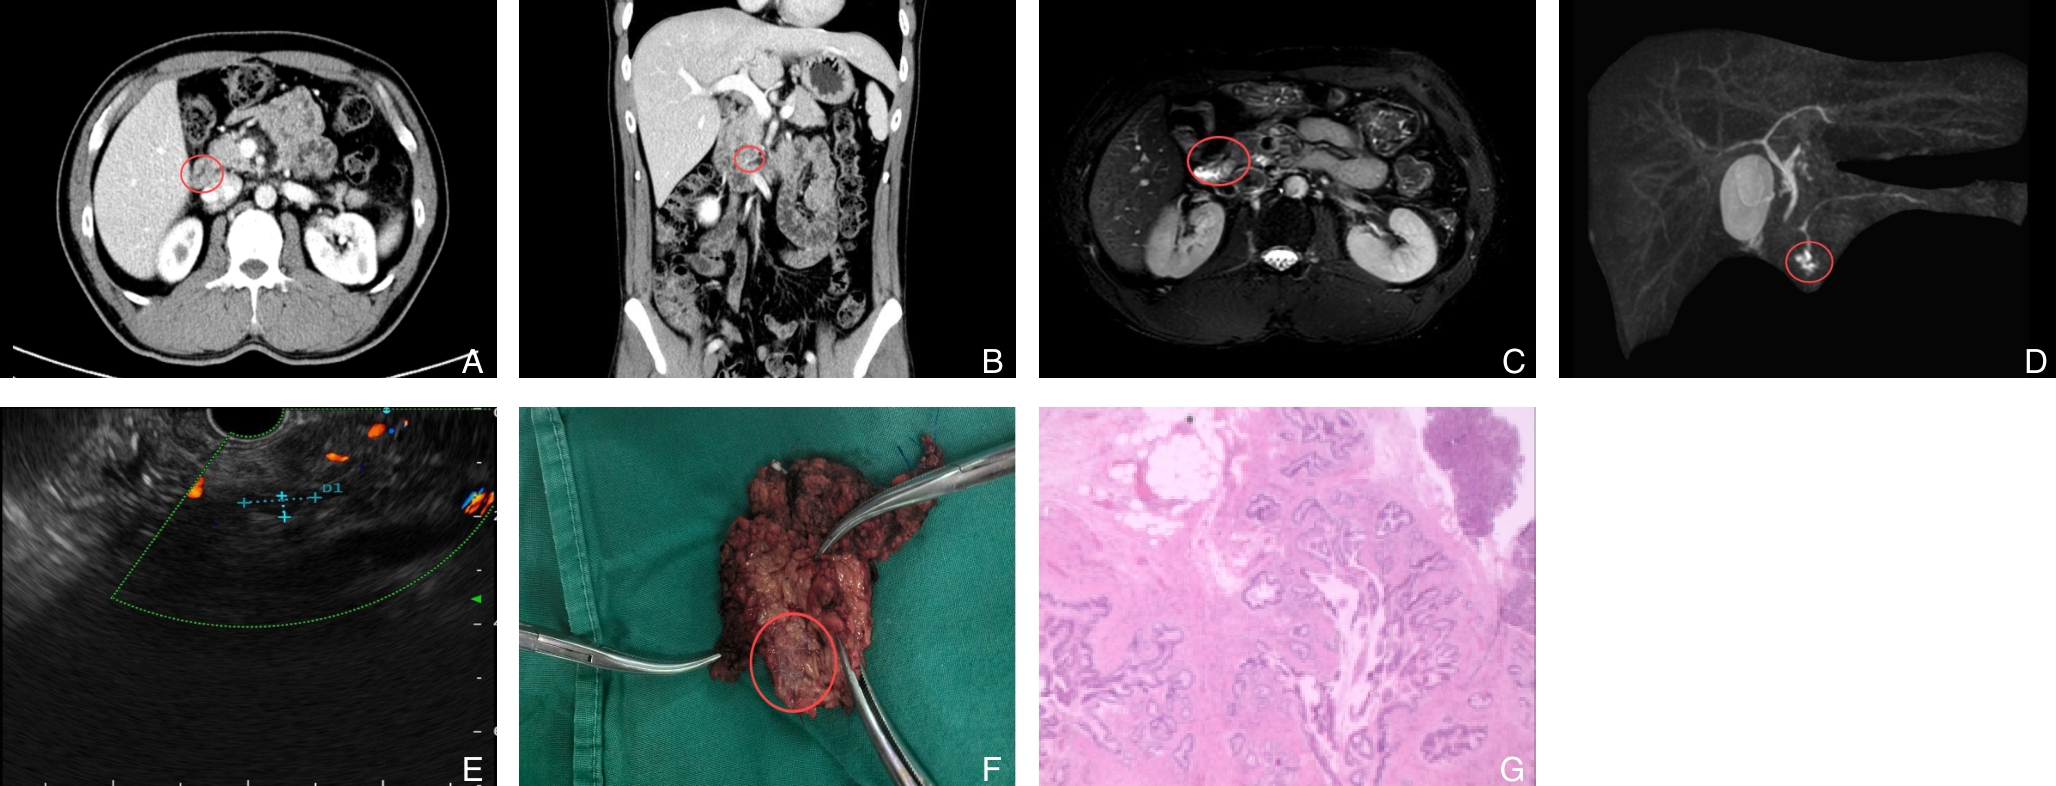

摘要:背景与目的 复发性急性胰腺炎(RAP)病因复杂,其中由寄生虫感染引起者极为罕见。胰腺阔盘吸虫侵入胰管导致梗阻并诱发RAP,目前国内尚无报道。本研究通过1例确诊病例,结合文献复习,探讨其临床特征、诊断难点及防治要点。方法 回顾分析湖南师范大学附属第一医院2023年收治的1例胰腺阔盘吸虫致RAP患者的临床资料,包括影像学、手术及病理学结果,并综述国内外相关文献。结果 患者为59岁女性,表现为反复上腹痛4年。影像学提示胰体尾部多囊性病变并胰管扩张,术前被考虑为胰管内乳头状黏液性肿瘤。行腹腔镜胰体尾及脾切除术后,病理证实导管内存在吸虫虫体及虫卵,最终确诊为胰腺阔盘吸虫感染。术后恢复良好,随访1年未再发胰腺炎。结论 胰腺阔盘吸虫是RAP罕见的病因,临床及影像学表现缺乏特异性,易误诊为胰腺囊性肿瘤。对于病因不明的RAP,尤其是有食用生食或野味史的患者,应重视寄生虫学检查,如粪便虫卵及血清抗体检测,以早期确诊并指导治疗。